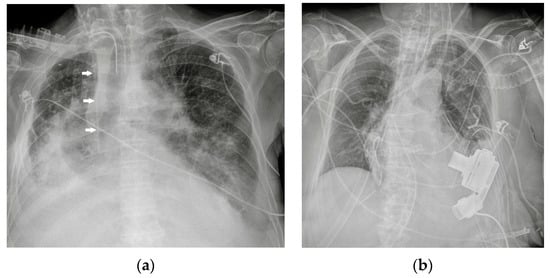

5. Cardiac Devices

5.2. Pacemaker (PM) and Automatic Implantable Cardioverter-Defibrillator (AICD)

5.3. Ventricular Assistance Devices (VADs)